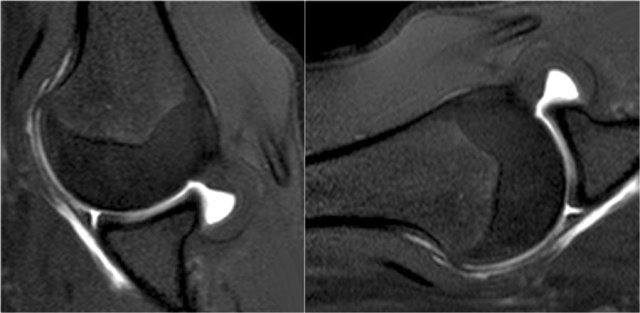

Reverse Bankart

CT-images in another patient show a reversed osseus Bankart in a patient with posterior dislocation.

Axial MR-arthrogram of a reverse Bankart.

Another example of a reverse Bankart.

Notice the detatched labrum at the 6-9 o'clock position on the sagittal MR-arthrogram.